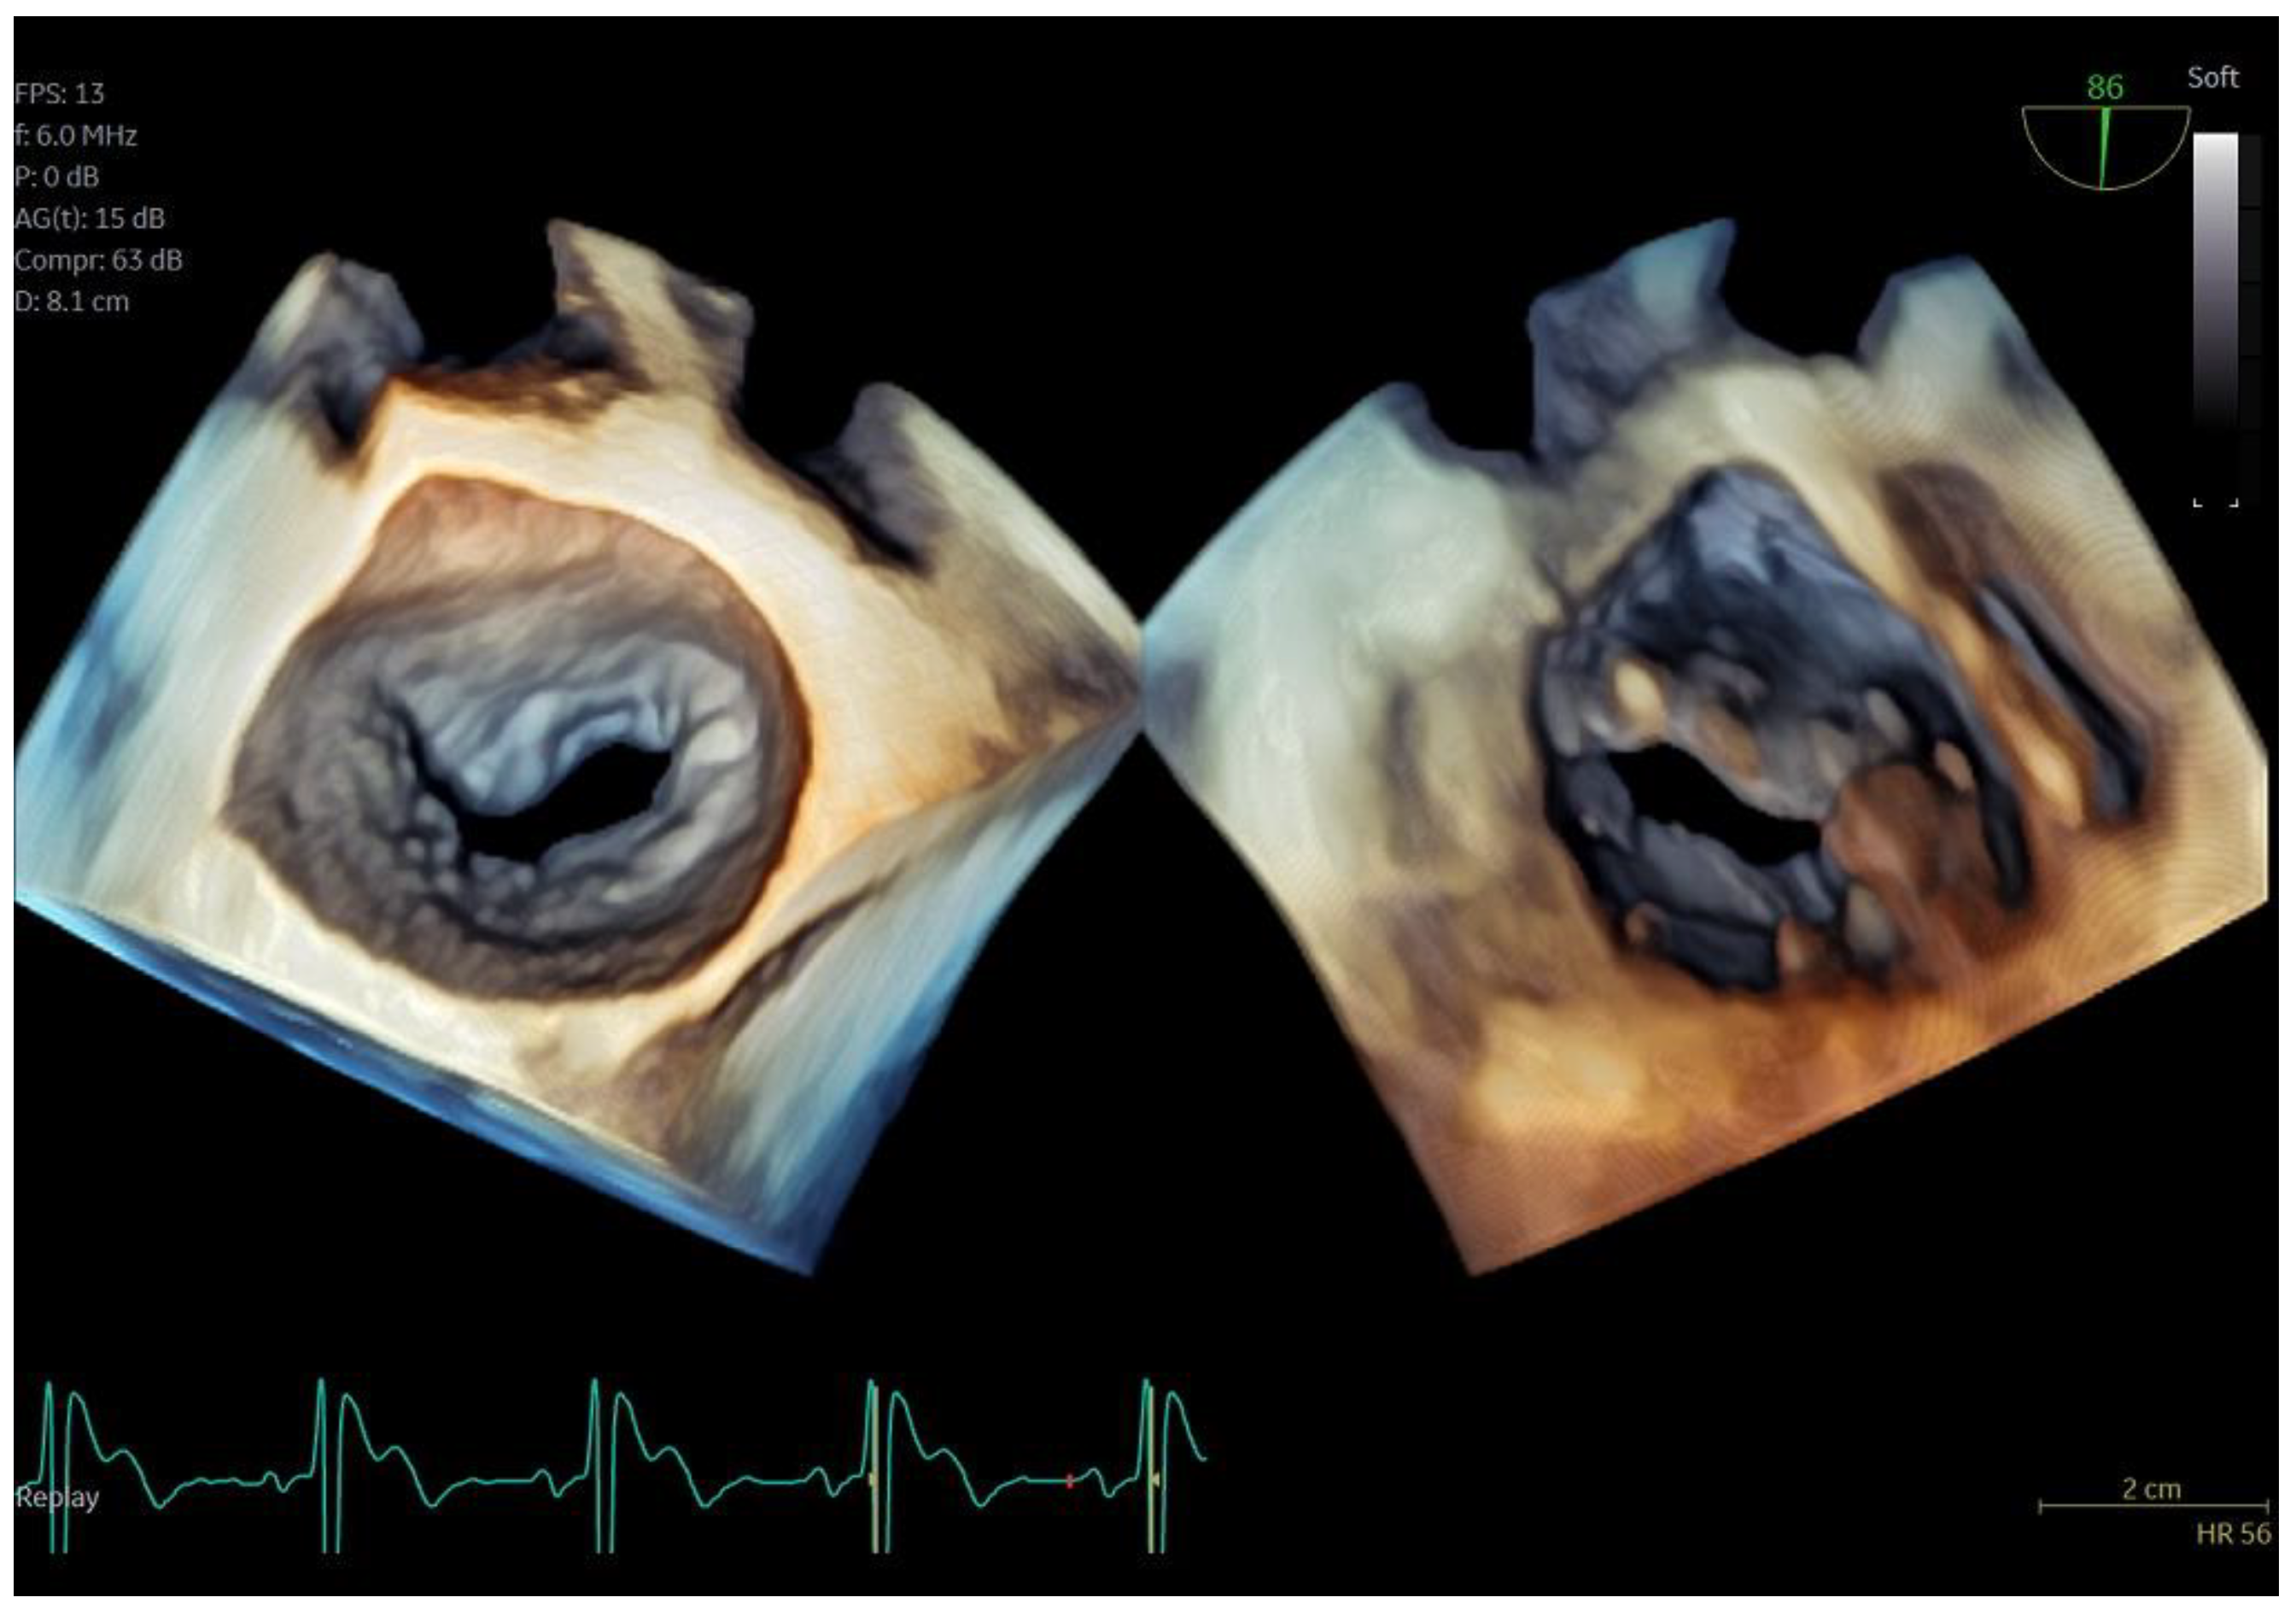

Figure 3.

Dual crop 3D volume-rendered atrial (left) and ventricular (right) views of normal mitral valve.

Figure 4.

(A) A 4D demonstration of a true−bicuspid aortic valve (red arrow), (B) Biplane 2D demonstration of a true−bicuspid aortic valve (red arrow), (C) Chronic dissection of descending aorta (red arrow showing the wall of the true lumen), (D) 3D volume-rendered color Doppler image showing the true (right arrow) and the false lumen (left arrow).

Regarding imaging quality, almost all patients exhibited excellent images without any compromise in resolution, obviating the need to confirm findings using the standard TEE probe (Figure 3 and Figure 4, video S5). Despite the one patient requiring additional sedation due to intense pharyngeal reflex, the quality of images obtained remained consistent across all cases. In 22 cases out of 30 included in this study, the 2D and 3D imaging quality received a score of 5 suggesting excellent imaging totally equal to the one acquired with the adult probe. In four cases, 2D and 3D images were commented as good with a score of 4 and in another four cases, while the 2D images were excellent, 3D images were again mentioned to be good, almost equal to the standard probe but not exceptional enough to receive a grade of 5 (Table 3).